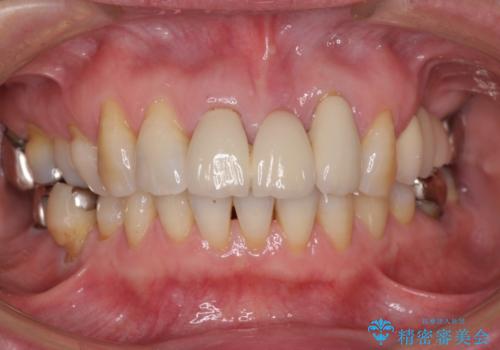

- 上の奥歯に装着されているブリッジが痛むとのことで来院された患者様です。

診察した結果、ブリッジの土台となっている歯が割れていたため、抜歯が必要となりました。

欠損している歯数が多いため、ブリッジによる補綴治療は困難と判断し、インプラントによる補綴治療を行うこととしました。

インプラントを埋入するために必要な骨の高さがなかったため、上顎洞底の粘膜を挙上しました。

手術後は処置部に痣や腫脹が出現したり、痛みが出たりしましたが、補綴治療後は咬み合わせが安定し、大変満足していただきました。